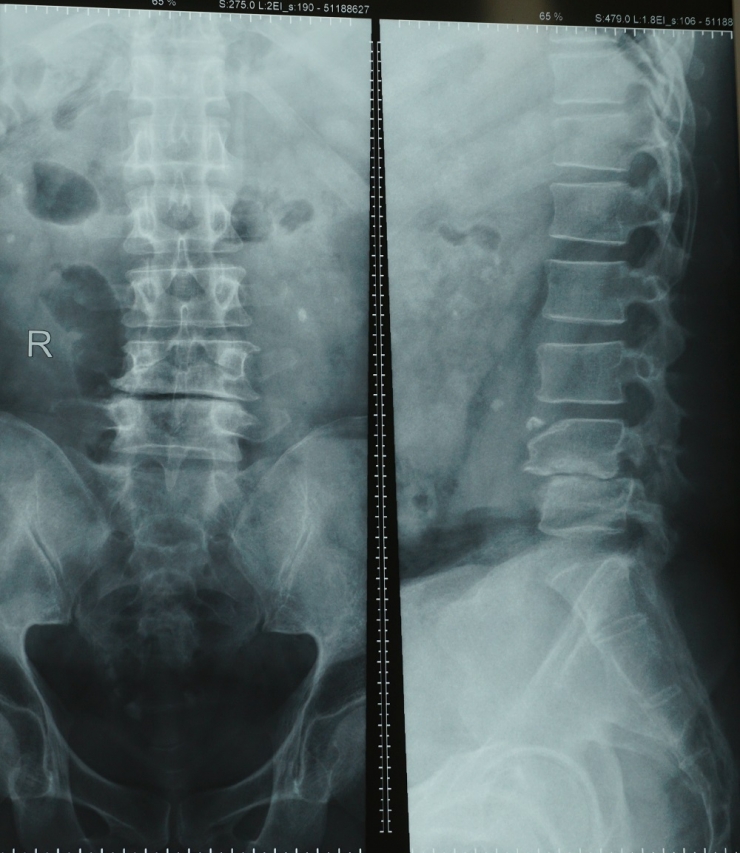

Hình chụp chụp X-quang của bệnh nhân

Qua thăm khám và chụp X-quang, MRI cột sống thắt lưng, các bác sĩ chẩn đoán bệnh nhân bị trượt đốt sống L4-5 loại khuyết eo, độ 1 – thoát vị đĩa đệm chèn ép rễ thần kinh cần phải phẫu thuật tránh yếu liệt hai chân và có thể bí tiêu tiểu.